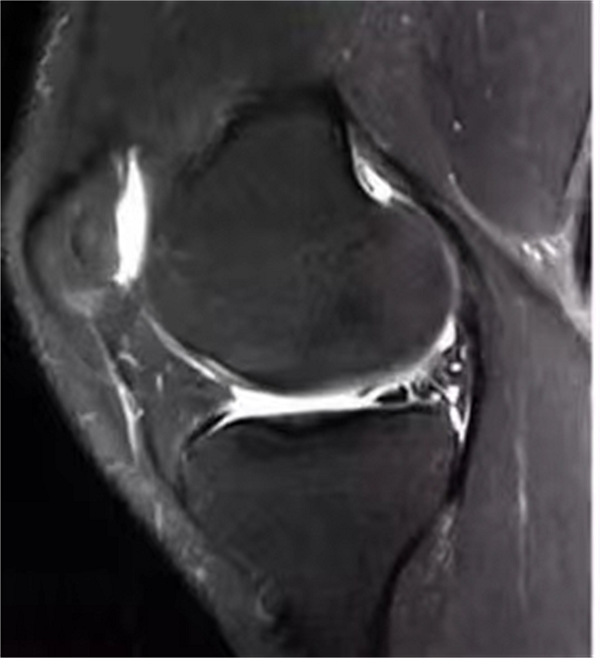

骨关节炎的治疗,主要有药物治疗、手术治疗、物理治疗三种,药物治疗具有一定局限性,手术治疗风险和创伤较大,物理治疗的范围有限,尤其是骨关节炎发展到很严重的程度,医生都只能望而却步。随着科技进步及国内外学者对PRP研究的逐渐深入,近几年PRP已在各临床学科取得巨大成效,其中骨病、创面、运动损伤、美容等领域的疗效尤为突出。富血小板血浆(Platelet-rich Plasma,PRP)简称PRP,是通过血液成分分离机从自体血中提取出来的血小板浓缩液。PRP中含有高浓度的血小板、纤维蛋白等物质。血小板被激活后,可释放多种生物活性物质,在促进组织愈合方面起着重要作用。它不仅为组织的修复提供了“浓缩的营养”,还为组织修复搭建了更好的修复环境。

应急总医院开展的PRP治疗,与其他医院最大的区别在于,结合每名患者的病情,每次抽取300-400毫升血液,离心出血小板(可治疗3-5次),将分离后的血液再输回体内,对人体没有任何伤害,也降低了医疗费用,治疗3个月后,对患者的疗效进行综合评估,视情调整治疗方案,达到最佳效果为止。